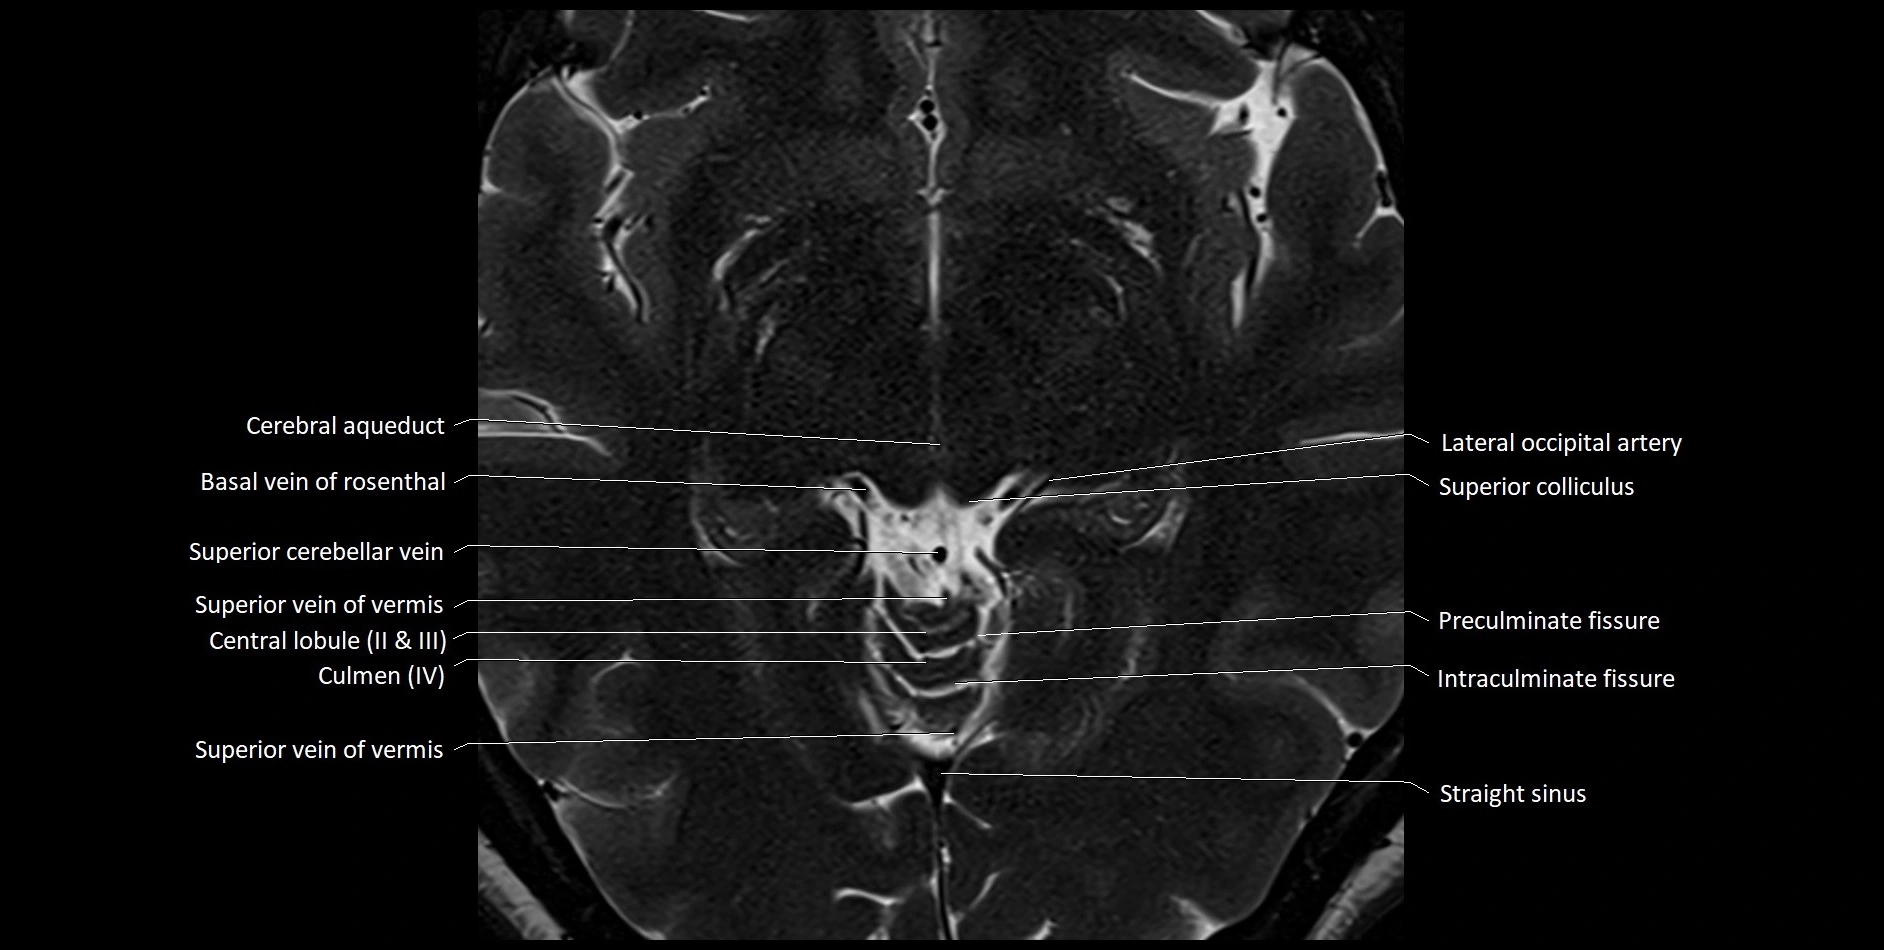

MRI images